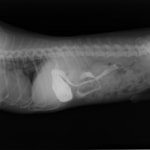

単純レントゲン検査:胃内ガス陰影・腸内ガスが少量認められる。

嘔吐が改善しないため、消化管バリウム造影検査を実施。

消化管バリウム造影レントゲン

バリウム造影3時間経過するも、胃内からバリウム排泄なく同日内視鏡検査を実施。